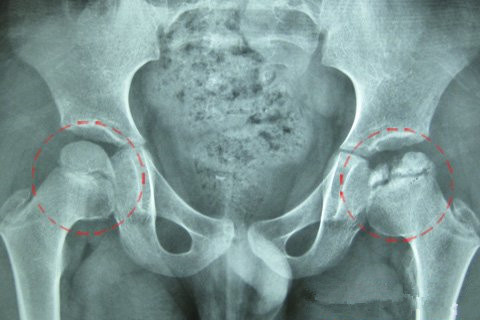

股骨头坏死作为常见的骨科顽疾,其病在关节而根在血管,股骨头堵塞的…… 【详情】